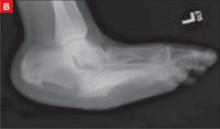

Late clinical signs of necrotizing fasciitis include cellulitis, skin discoloration, discharge of “dishwater” fluid, blistering, and hemorrhagic bullae. Findings of crepitus and soft tissue air on plain radiographs are seen in 37% and 57% of patients, respectively.4 Our patient’s X-ray findings revealed extensive gas pockets within soft tissue and osteomyelitis changes of the 5th metatarsal head.